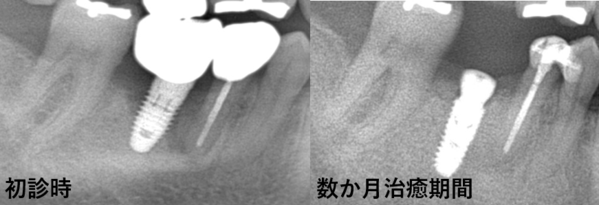

右下6番相当部のみのX線写真です。

6番インプラント周囲の骨欠損が確認できます。

インプラント撤去後、周りの組織を清掃しつつ、骨補填材による骨造成(GBR:Guided Bone Regeneration)を行います。

この状態で数か月の治癒期間を設け、その後新たなインプラントを埋入します。

さらに数か月の待機期間を経て、最終的な被せ物を装着した状態が下の写真です。